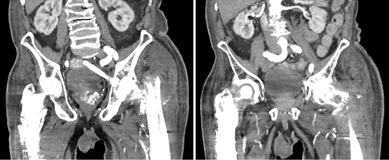

与患者和家属讨论后,他们希望继续进行非手术措施以促进骨折愈合。初次受伤后4个月的连续影像学检查显示,骨折已经愈合。